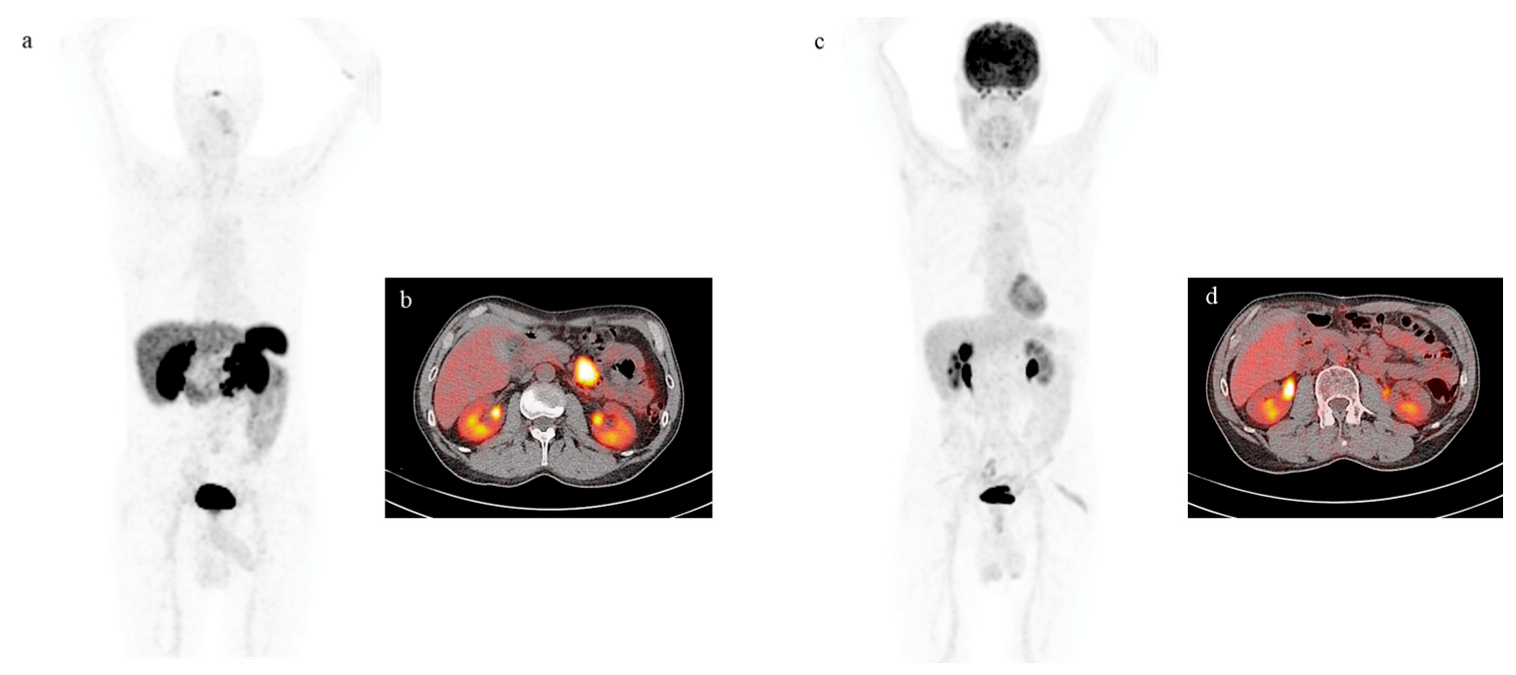

4. Functional Imaging by SST Analogs

5. Imaging Analysis

6. Functional Imaging by 18F-FDG PET/CT

7. PRRT by Radiolabeled Somatostatin Analogs